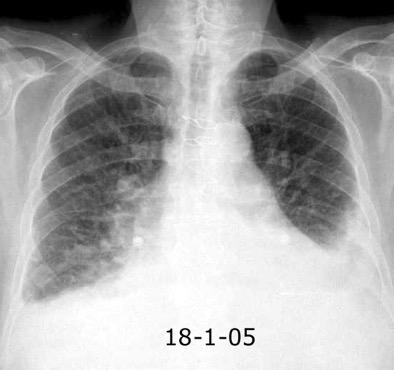

Síndrome de afectación postcardiaca (postcardiac injury)

Post infarto 1-7 % (Dressler)

Trauma cerrado Implantación marcapasos

Cirugía cardiaca. 17-31% (Post.pericardiotomía)

3707 pacientes 29 Derrames (0,78%) > de 25% del hemitórax

Todas menos 2 Izdos.

Angioplastia

By-pass coronario 21-10-03